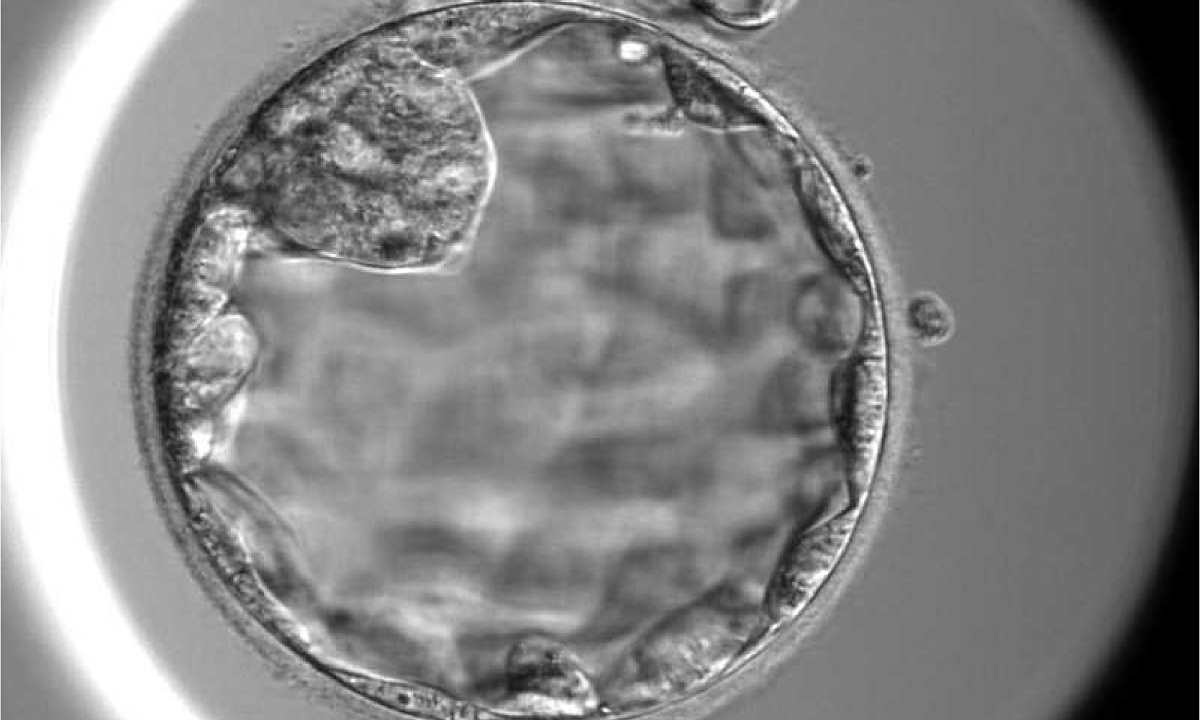

Bác sĩ Thủy kích thích buồng trứng cho bệnh nhân, thu 19 trứng, hầu hết có hình thái móp méo, bào tương rỗ, không phát triển đến giai đoạn trưởng thành. Chuyên viên phôi học nỗ lực lọc rửa, tiếp tục nuôi cấy toàn bộ trứng trong môi trường tối ưu và chọn lọc được 14 trứng đủ điều kiện để thụ tinh cùng tinh trùng của người chồng. Kết quả thu được 3 phôi ngày 3, tiếp tục nuôi lên giai đoạn ngày 5 thì hai phôi ngừng phát triển, còn phôi duy nhất vượt qua sàng lọc tự nhiên khắc nghiệt. Phần mềm trí tuệ nhân tạo (AI) chấm điểm chất lượng phôi loại 3, mức độ trung bình.

Hình ảnh phôi ngày 5 được nuôi cấy tại IVF Tâm Anh TP HCM. Ảnh: Thu Thảo